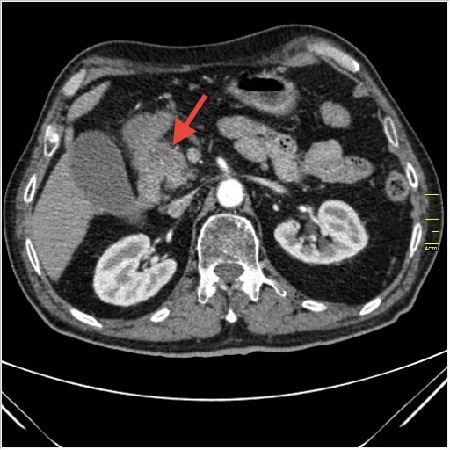

Мужчина 62 года с желтухой

Опухоль головки поджелудочной железы, расширение холедоха и панкреат. протока (Double Channel sign)

Карциномы панкреас гиподенсны на КТ с болюсом, т.к. содержать много соединительной и фиброзной ткани, в отличие от нормальной ткани железы, которая (как любая железа) хорошо васкуляризирована. Поэтому если видим в панкреас солидное гиподенсное образование - всегда настораживает на предмет рака. Второй момент: обязательная оценка взаимоотношения опухоли к ВБА и ВБВ, на предмет оценки операбельности.